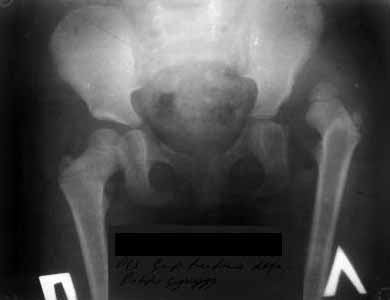

результат через 2 года, но повторяюсь осталось так называемое недопокрытие впадиной головки бедра но клинически результат отличный.